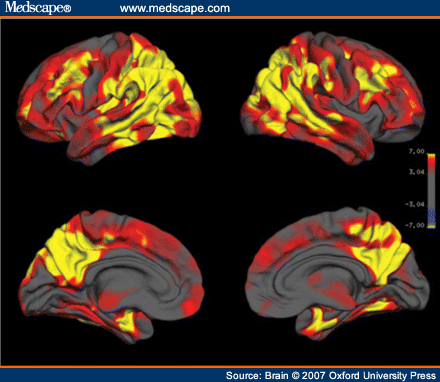

Emotional control may be difficult, leading to personality changes. Patients also show progressive motor, cognitive, moo and behavioral changes over a period of 5-years. Because vascular dementia can cause symptoms and signs similar to those of DLB, brain MRI is indicated to distinguish DLB from vascular dementia. Patients with vascular dementia often have white matter lesions on MRI scans, whereas patients with DLB do not. CSF examination is not required in routine cases.